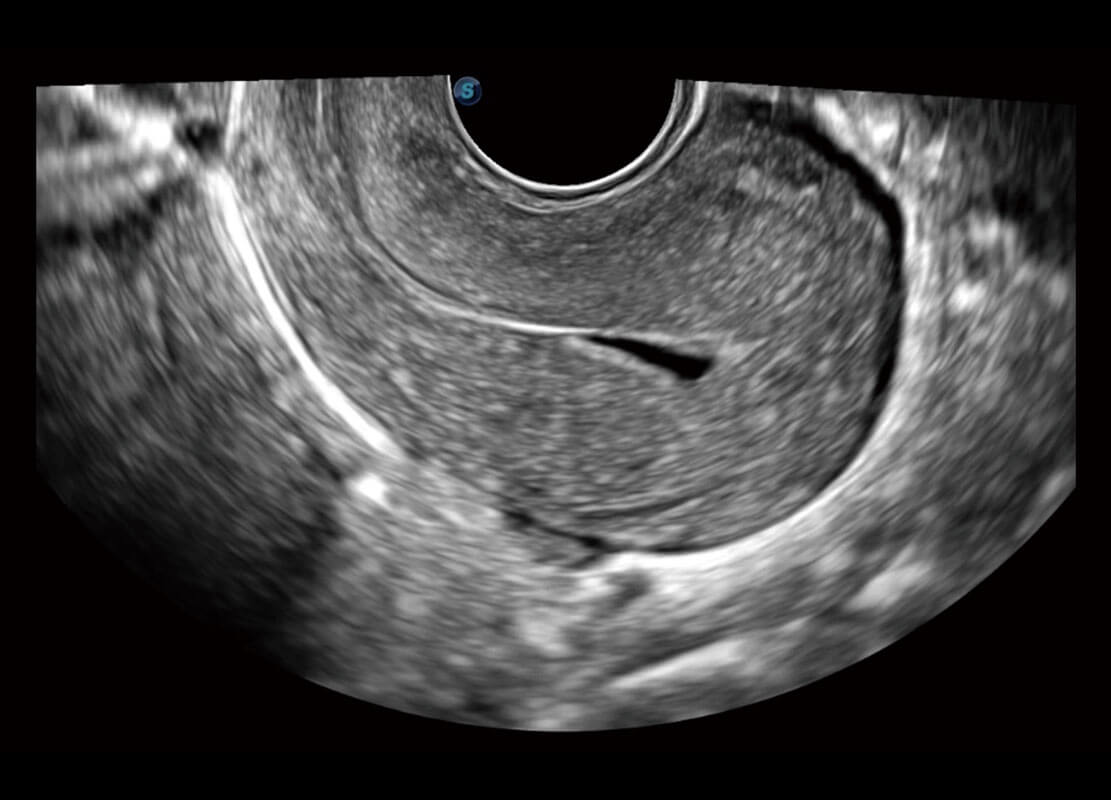

腔内妇科-宫腔分离

腔内妇科-卵巢